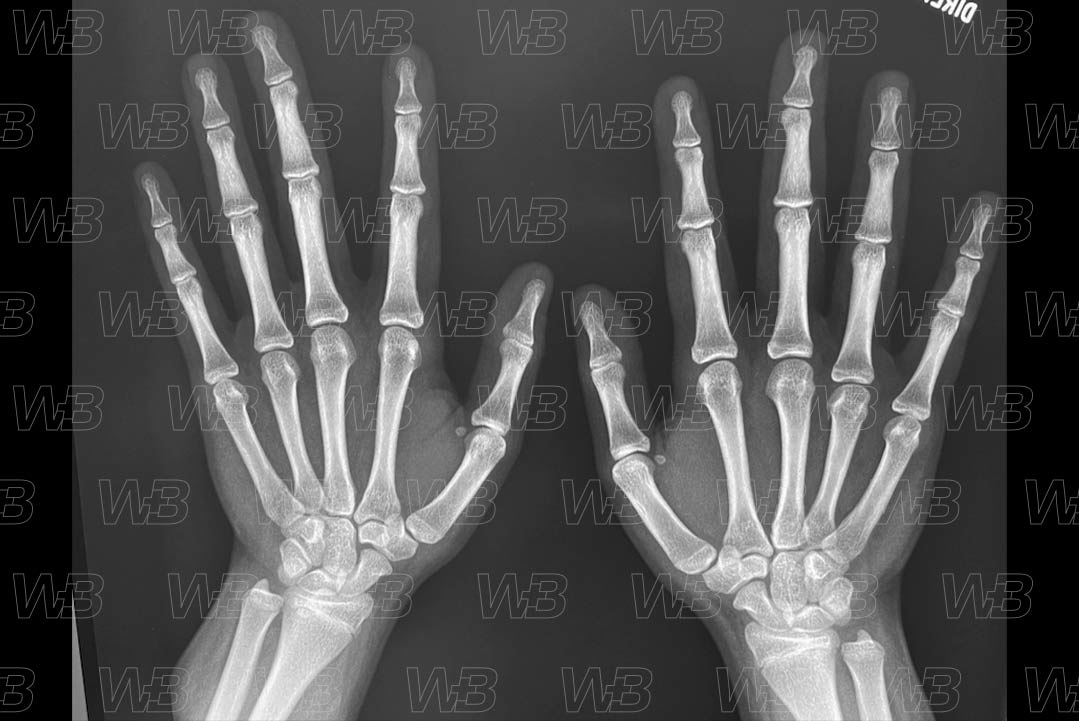

Atlas idade óssea - Feminino - 15 anos

RADIOGRAFIA MÃOS E PUNHOS [cms-watermark]

Feminino

15 anos:

• Fusão de todas epífises das falanges e metacarpos.